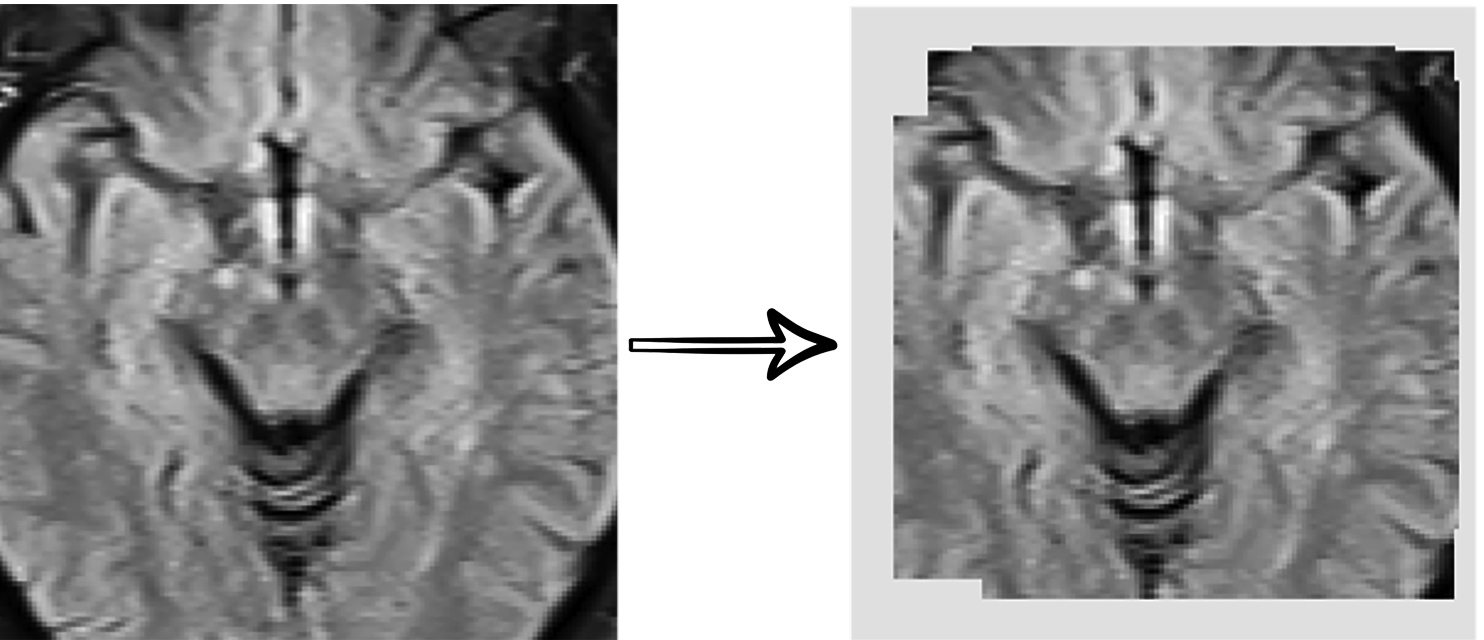

5.3 Self-Supervised Training Results Visualization

Refer to caption

Figure 5: Reconstruction results of the combination of various transformations over images through the self-supervised network.